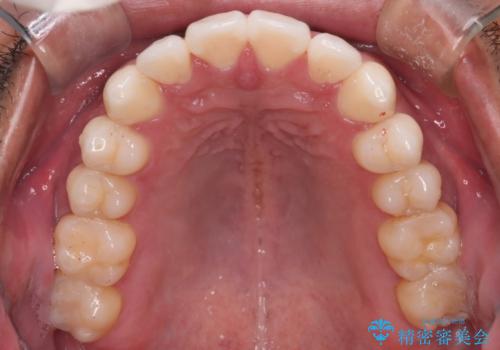

【審美装置】開口(オープンバイト)を改善

- 全体的に歯並びをよくしたいとのことで来院されました。初診時、患者様はセラミック矯正とワイヤー矯正で迷われていました。

開口(オープンバイト)のため噛み合わせを考慮してワイヤー矯正を提案させていただきました。

IPR(歯と歯の間を削る処置)と顎間ゴムを行い歯並びを整える治療計画を立てました。